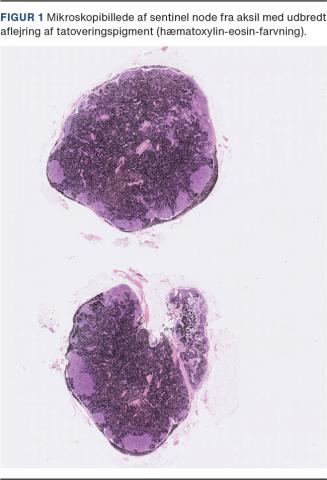

En 31-årig kvinde blev diagnosticeret med brystkræft efter fund af en 8 mm stor cancer. Patienten fik neoadjuverende kemoterapi, og på grund af sin unge alder valgte hun at få lavet bilateral mastektomi og rekonstruktion. I forbindelse med sentinel node-dissektion fandt man en bemærkelsesværdig mørk lymfeknude, som rejste mistanke om malignt melanom. Lymfeknuden blev sendt til histologisk undersøgelse og viste sig at være fyldt med tatoveringsblæk (Figur 1), men uden tegn på metastaser fra malignt melanom eller brystkræft. En meget kraftigt pigmenteret lymfeknude kræver særlig opmærksomhed i forbindelse med mikroskopi, idet tatoveringspigment kan kamuflere eventuelle metastaser. Immunhistokemisk undersøgelse for lavmolekylær cytokeratin er en del af den diagnostiske procedure og bidrager til endelig diagnostik.

Patienten havde flere håndfladestore tatoveringer på armene, som formentlig var ophav til farven i hendes lymfeknude.